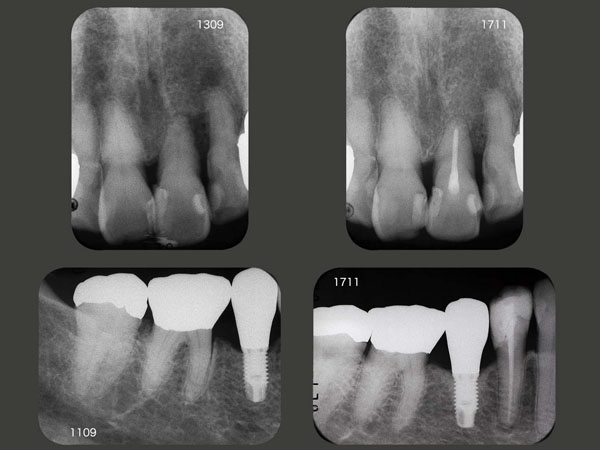

歯周外科処置を行った左上1の歯槽骨は改善傾向を示している.これに対し,インプラント周囲の歯槽骨は緻密化し,将来何となく心配である.デンタルX線写真からみてとれるように,神様が作られた天然歯と人間が作ったインプラントでは,やはり違うと言わざるを得ない.安易な抜歯は避けるべきである.